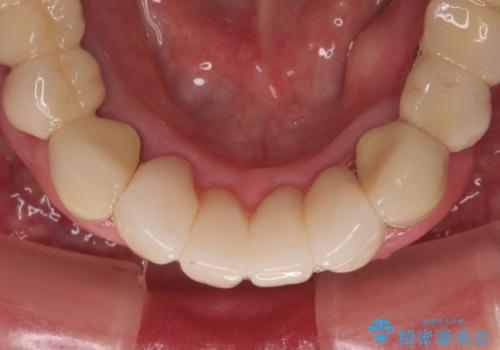

臼歯部の治療も必要と判断されましたが、前歯部を中心とした審美領域をオールセラミッククラウンによる補綴治療を行うこととしました。

帰国時のみの治療であったため、治療期間は長くなりましたが、最小限の来院回数で、気になっていた前歯をきれいに整えることができました。